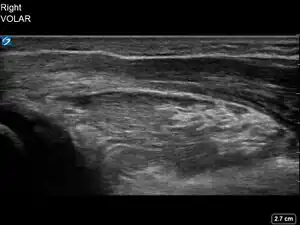

| 4 | Pronator quadratus hematoma[17][14][18] | ![]() Ultrasound view of pronator quadratus hematoma (PQH) sign (area inside red oval) which is identified by an increased thickness and brighter appearance of the pronator quadratus muscle compared to the pronator quadratus muscle of the unaffected forearm. |

Ultrasound Scanning for Pronator Quadratus Hematoma Sign

While the patient has their affected forearm supinated at least 90 degrees, maintain the probe perpendicular to the skin, align the probe with the metaphysis of the distal radius, and increase the depth to 4 cm.

Record a 4 second video while slowly sweeping across the volar (palmar) aspect of the distal forearm until the metaphysis of the distal ulna is in the field of view.

Review the video to obtain an image of the largest section of the pronator quadratus muscle, which is typically the mid-portion of the sweep.

Repeat steps 1-3 with the unaffected forearm for comparison. Compare the thickness and appearance of the pronator quadratus muscle on both sides.

Note whether the affected forearm has a hematoma of the pronator quadratus muscle.